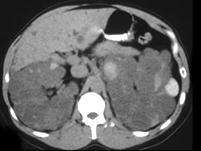

女,52岁,腰部酸胀,根据影像图像,判断其最可能的诊断 ( )A、肾脓肿B、肾盂癌伴出血C、肾细胞癌D、多囊肾E、多房性肾囊肿

问题 女,52岁,腰部酸胀,根据影像图像,判断其最可能的诊断 ( )

选项 A、肾脓肿 B、肾盂癌伴出血 C、肾细胞癌 D、多囊肾 E、多房性肾囊肿

答案 D